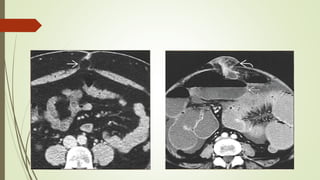

HERNIAS INTERNAS

 Las hernias internas implican la protrusión de las vísceras a través del peritoneo o

mesenterio y en un compartimiento en la cavidad abdominal.

 La presentación más común es una obstrucción intestinal aguda de los pliegues

del intestino delgado que se desarrolla a través de aberturas normales o

anormales.

 Los orificios hernianos responsables son generalmente estructuras anatómicas

preexistentes, tales como agujeros, cavidades y fosas.

 Defectos patológicos del mesenterio y del peritoneo visceral, causados por Los

mecanismos congénitos, la cirugía, el trauma, la inflamación y la circulación, son

también posibles orificios de herniación.

HERNIAS PARADUODENAL.

 Las fosas paraduodenales se originan como anomalías peritoneales

congénitas debido al fracaso de la fusión mesentérica con el peritoneo

parietal y una rotación anormal asociada durante el encarcelamiento del

intestino delgado bajo el colon en desarrollo

HERNIAS PARADUODENAL